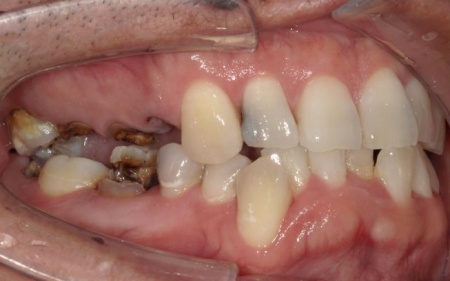

とくに、右上奥歯は前から4番目と6番目の歯、左上奥歯は前から4番目・5番目・6番目・8番目の歯が著しく傷んでおり、温存が難しいと考えられます。

また、右下の一番奥の歯(親知らず)は歯の根だけが残り、細菌感染が広がるリスクが高い状態です。

まずは、温存が難しいと判断した以下の歯を抜きます。

右上

・4番目(第1小臼歯)

・6番目(第1大臼歯)

左上

・5番目(第2小臼歯)

・8番目(第3大臼歯)

右下

・8番目(親知らず)

感染が周囲に広がらないよう配慮しながら、慎重に抜歯を行いました。